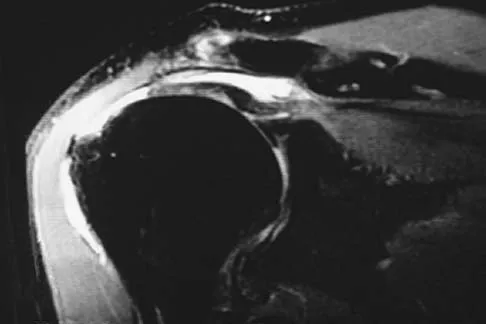

A 32-year-old woman has had pain and a visibly growing mass in the shoulder for 3 years but denies any history of trauma. Examination reveals a swollen, boggy shoulder mass. The AP radiograph and MRI scan are shown in Figures 20a and 20b. Figures 20c through 20e show a portion of the excised mass and the photomicrographs of the biopsy specimen. What is the most likely diagnosis?

Explanation